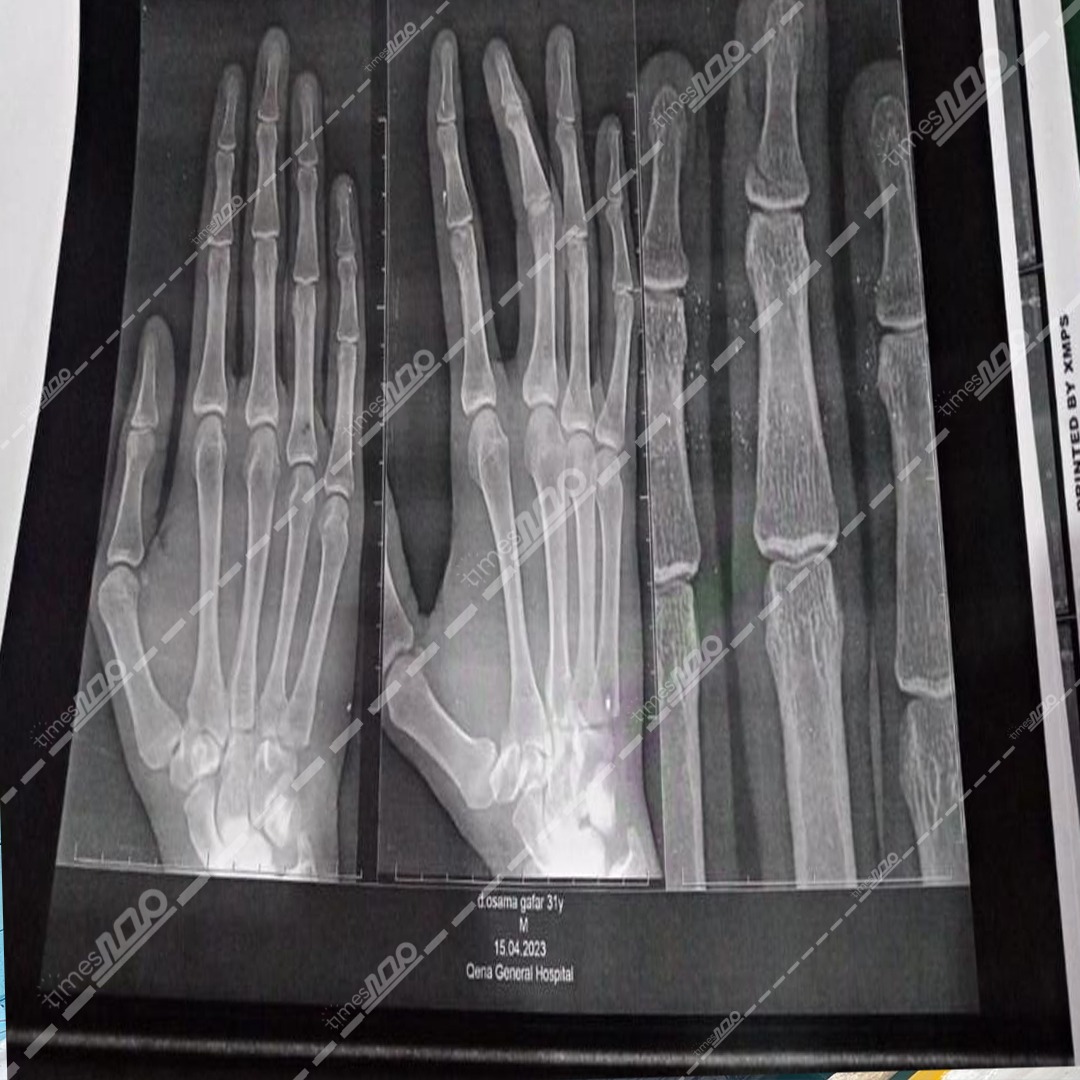

ننشر صور أشعة الطبيب المعتدى عليه من أسرة مريض بمستشفى قنا العام (خاص)

حصل "مصر تايمز" على صور الأشعة التي أجراها طبيب جراحة على يديه، بعد التعدي عليه من قبل أسرة مريض أثناء عمله داخل مستشفى قنا العام، والتي وضحت كسر في أحد صوابعه.

وعلى الفور انتقلت قوة أمنية برئاسة المقدم محمود حمد الله، رئيس مباحث قسم قنا، إلى المستشفى وتبين إصابة طبيب جراحة، بكسر في أحد صوابعه وكدمات بالوجه إثر التعدي عليه من أسرة مريض.